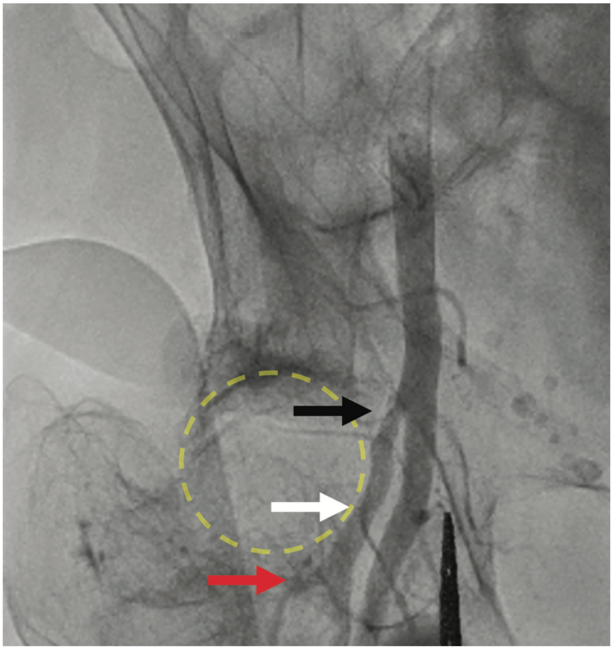

Arterial access for this patient was complicated by bilateral arm contractures. The intended area of right common femoral artery access was identified using the anterior iliac spine and pubic symphysis as landmarks, and a radiopaque instrument was visualized under fluoroscopy to confirm optimal site of arterial entry at the midpoint of the femoral head. Using ultrasound guidance at this site, a bifurcation was identified, and the artery proximal to the meeting point of this bifurcation was visualized and accessed using micropuncture needle. A femoral angiogram was then performed, revealing that the patient had an unusually high bifurcation of the superficial and profunda arteries at the most superior aspect of the femoral head (Figure 1). This made evident that the vessels distal to the bifurcation visualized on ultrasound were actually large branches from the profunda femoris artery (Figure 2). With knowledge that site of entry was in the profunda femoris artery, decision was made to proceed with upsizing to 6 French sheath. The remainder of the procedure was performed without further difficulties. Findings were significant for distal left anterior descending (LAD) coronary artery stenosis that was moderate in severity on coronary angiography, and for apical aneurysm and reduced ejection fraction on left ventriculogram.